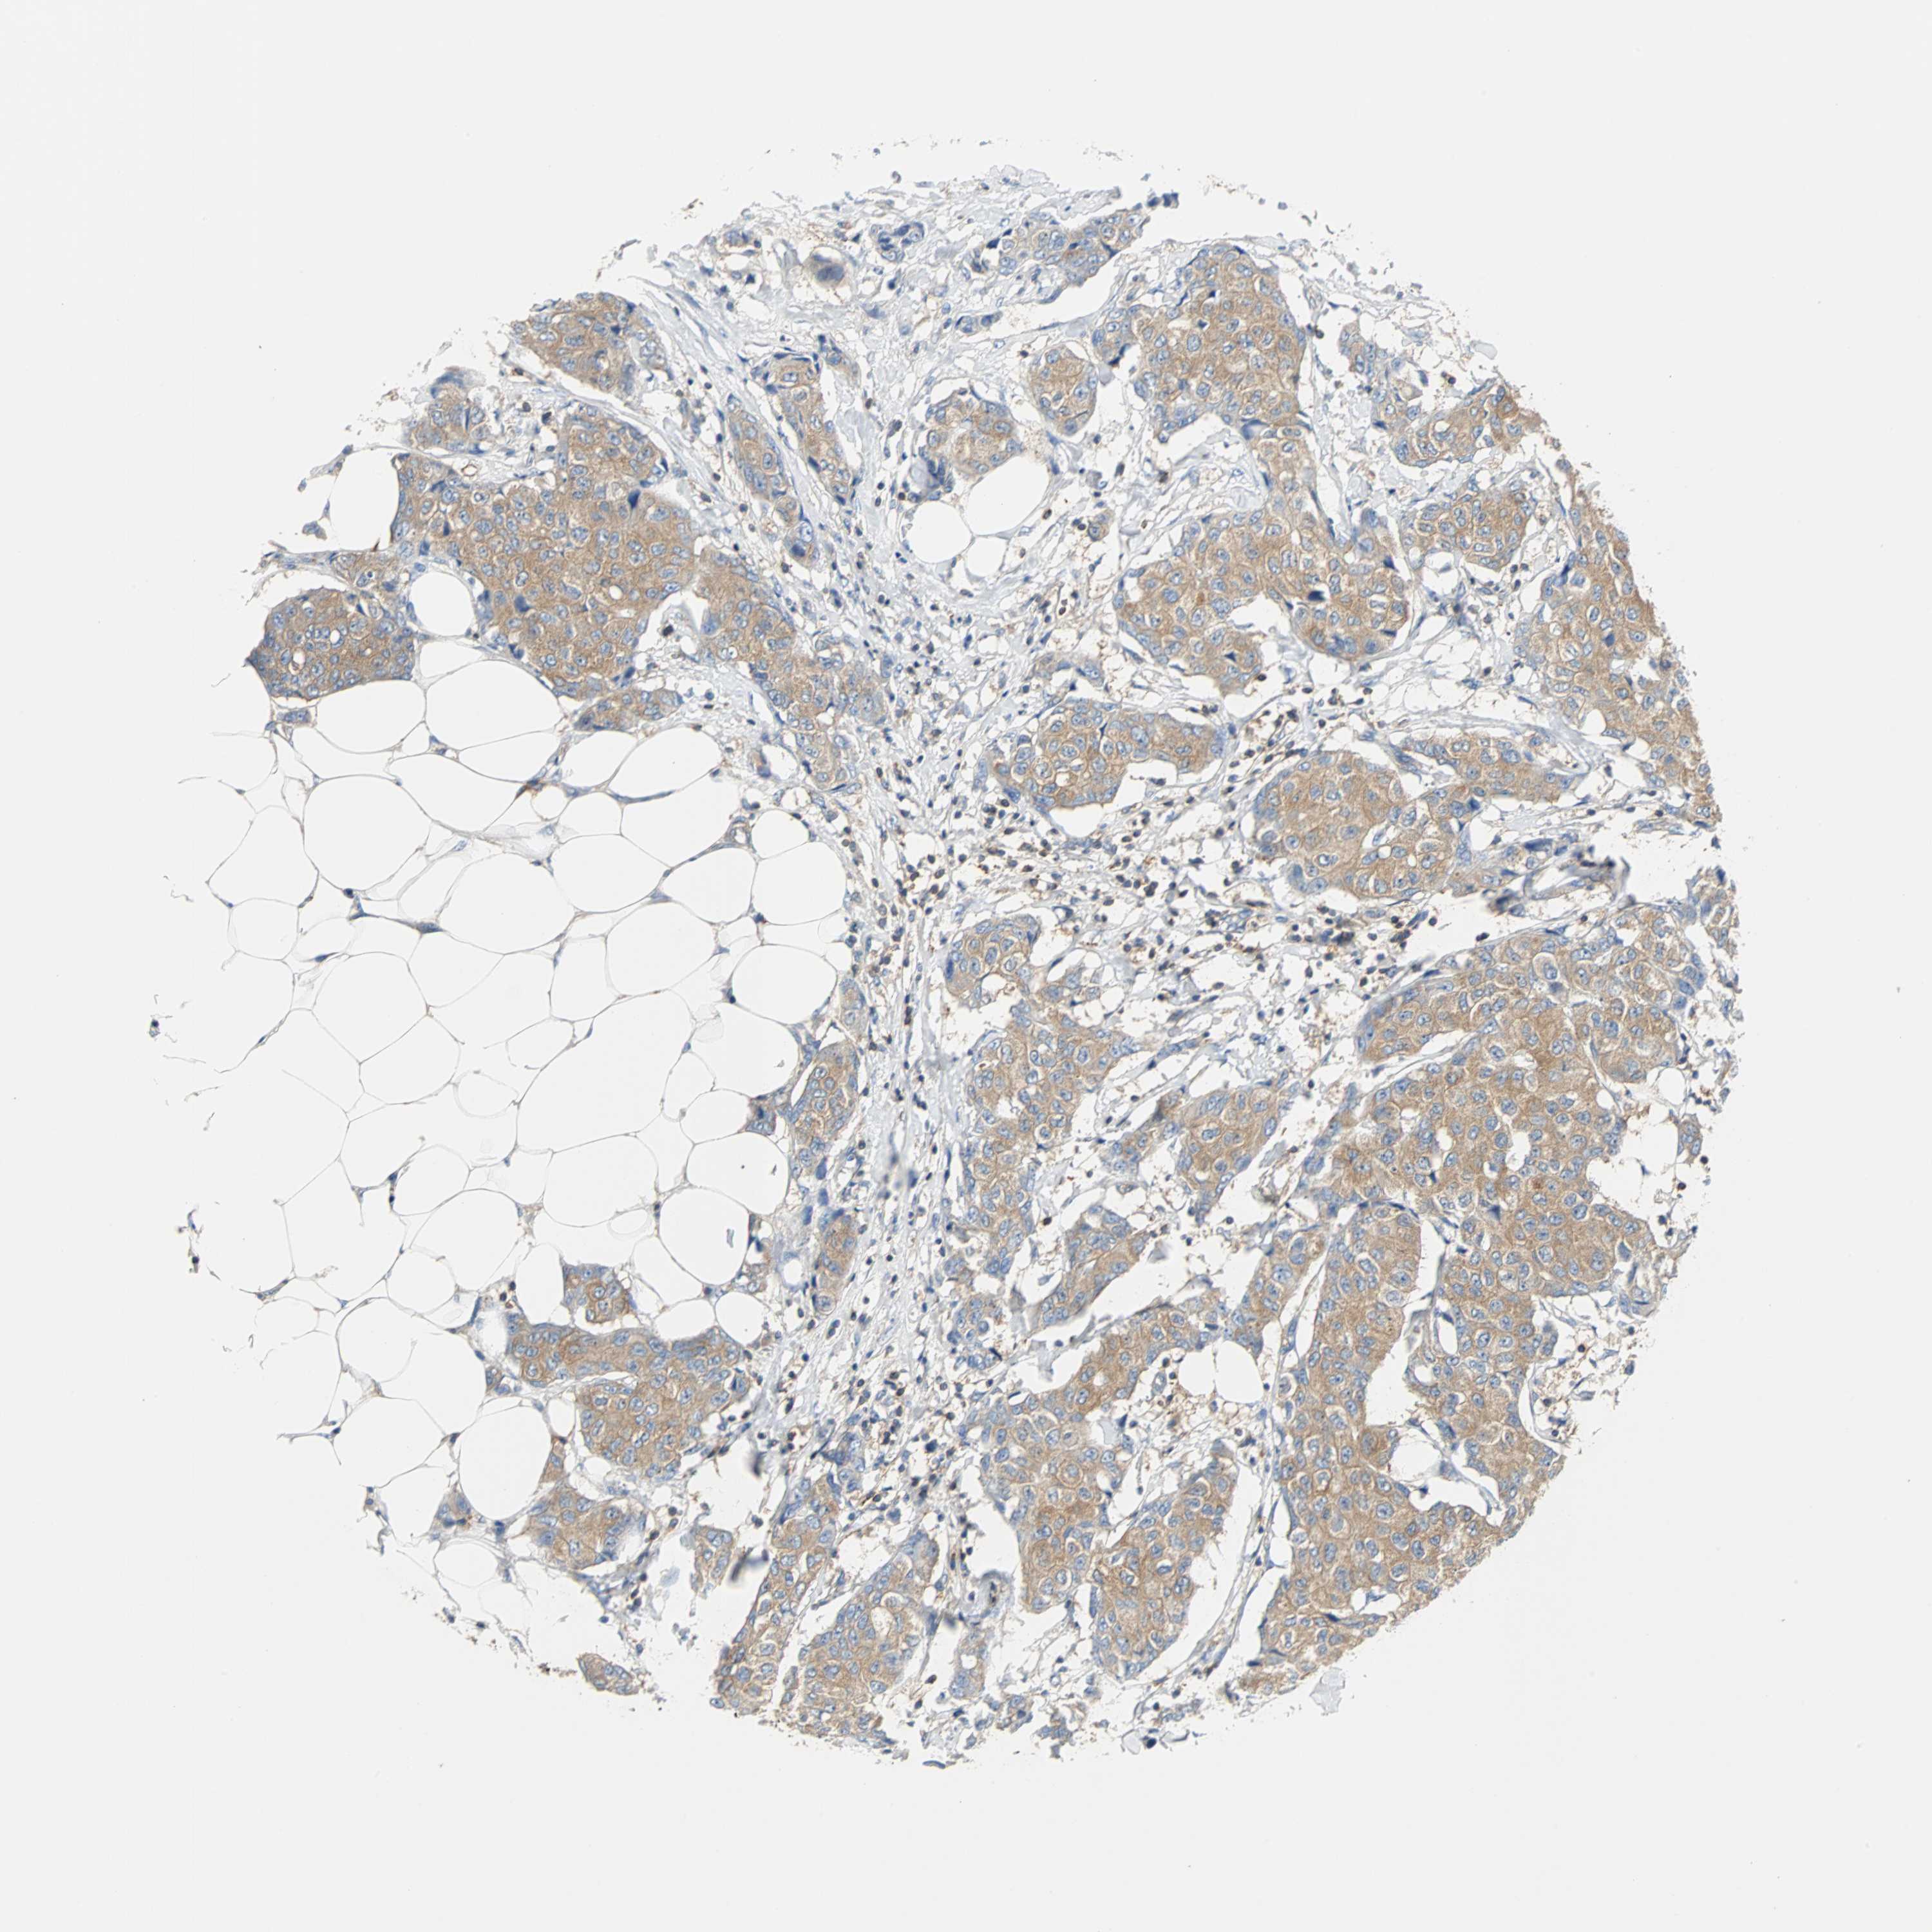

BRCA TCGA BRCA VALIDATION PROTEIN EXPRESSION